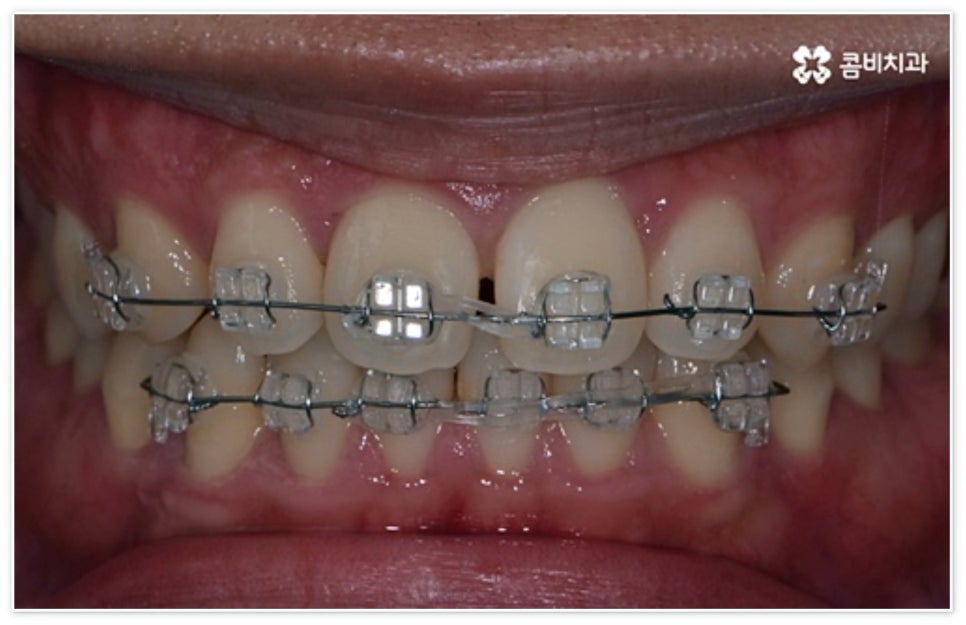

만약 구강 질환으로 인한 손상이 아직 발생하지 않은 상태이거나 구조적인 원인으로 인해 앞니 벌어짐 이 지속적으로 진행되어 점점 더 심해지고 있는 상태라면 말씀드린 레진이나 보철 수복 치료는 적합하지 않고 교정 치료를 통해 이를 바로잡아 줄 필요가 있습니다. 사실 교정 치료는 시간이 좀 더 걸리긴 하지만 치아에 손상을 주지 않고 이를 움직여 벌어진 공간을 자연스럽게 닫아줄 수 있는 방법이기 때문에 정교한 계획을 통해 무리하지 않게 진행되고 사후 유지 관리가 철저하게 된다면 보다 확실하게 벌어진 앞니를 개선하는 치료법이 될 수 있는데요.

혹시 교정에 대한 막연한 두려움으로 치과 내원 자체를 꺼리시는 분이 있다면 상황에 따라 부분 교정을 통해 보다 빠르고 간편하게 앞니 벌어짐 현상을 개선할 수 있는 경우도 있으니 먼저 검진과 상담부터 진행해 보시고 자신에게 필요한 치료가 어떤 것인지 명확하게 알아보시길 권유드리고 있어요.

환자분들에 따라 다르지만 통상적으로 전체 교정이 1년에서 2년 반 정도 소요된다면 부분 교정은 6~8개월 정도로 기간 단축이 가능하여 치료에 대한 부담을 줄일 수 있으며 대부분 발치 과정 없이 필요한 부위에만 브라켓을 부착하는 만큼 불편함이 적고 구강 관리도 용이한 편이니 (사진에서 살펴볼 수 있는 케이스) 이에 대해서 자세히 알아보시면 좋을 거예요. 물론 누구나 가능한 것은 아니고 개인의 구강 상태에 따라 진행을 해야 하므로 꼼꼼한 검진과 충분한 상담부터 받아보시길 권유드리고 있습니다.